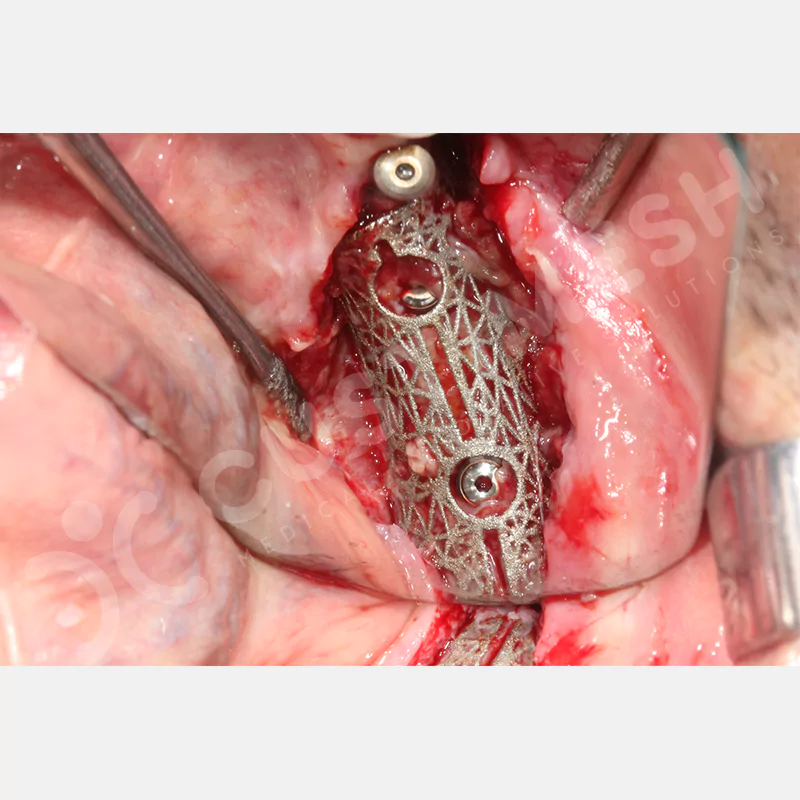

Dental implant uygulanamayan hastalarda kemik rejenerasyonunu sağlamak üzere geliştirilen kişiye özel titanyum mesh, kemik augmentasyon işlemlerinde greft materyalinin korunması ve yeni kemik oluşumunun desteklenmesi amacıyla kullanılan, hastanın kendi anatomisine tam uyumlu titanyum bir bariyer sistemidir.

Medikal sınıf titanyumdan, hastanın bilgisayarlı tomografi verileri kullanılarak CAD yazılımlarıyla tasarlanan ve 3D baskı teknolojisiyle üretilen bu yenilikçi çözüm, özellikle kompleks kemik defektlerinde standart meshlerin sağlayamadığı üstün mekanik stabilite ve mükemmel adaptasyon özellikleri sunar. Anatomik yapıya tam uyum sağlayarak greft materyalinin yerinde kalmasını garanti ederken, optimal vaskülerizasyonu destekleyerek kemik rejenerasyon sürecini hızlandırır.

- Grade 23 Medikal Sınıf Titanyum Malzeme

- Optimum Şekilde Tasarlanmış Vida Delikleri

- Özel Olarak Tasarlanmış İmplant ve Kondenzasyon Delikleri

- Çıkarımı Kolaylaştırmak için Özel Tasarım

- Palatinal Yada Lingualden Vidalama İhtiyacı Olmaması